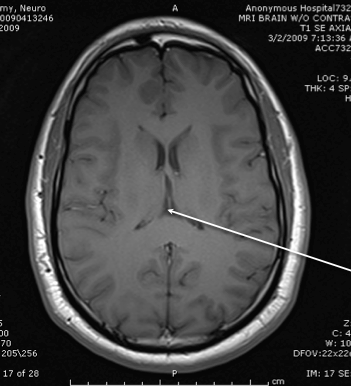

posterior horn of the internal capsule

thalamus

anterior limb of the itnernal cpasule